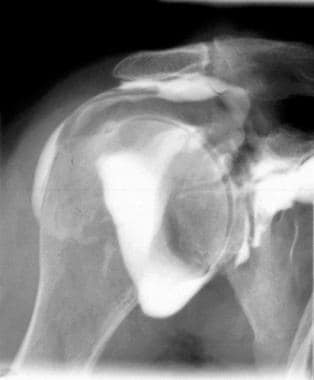

Figure 1: Rotator Cuff Tear This rotator cuff tear is seen in the The muscle is lit up in bright white and you can see a dark spot indicating the Figure 2: Partial Rupture This is a partial rupture of one of the rotator cuff The red arrow indicates the rupture Figure 3: Complete Rotator Cuff Tear

When a rotator cuff tear goes unrepaired, the ball part of the joint tends to drift higher in socket, causing arthritis over Superior capsule reconstruction restores the alignment of the shoulder joint and normalizes its mechanics, which may slow progression of the Learn More Rotator Cuff Tears